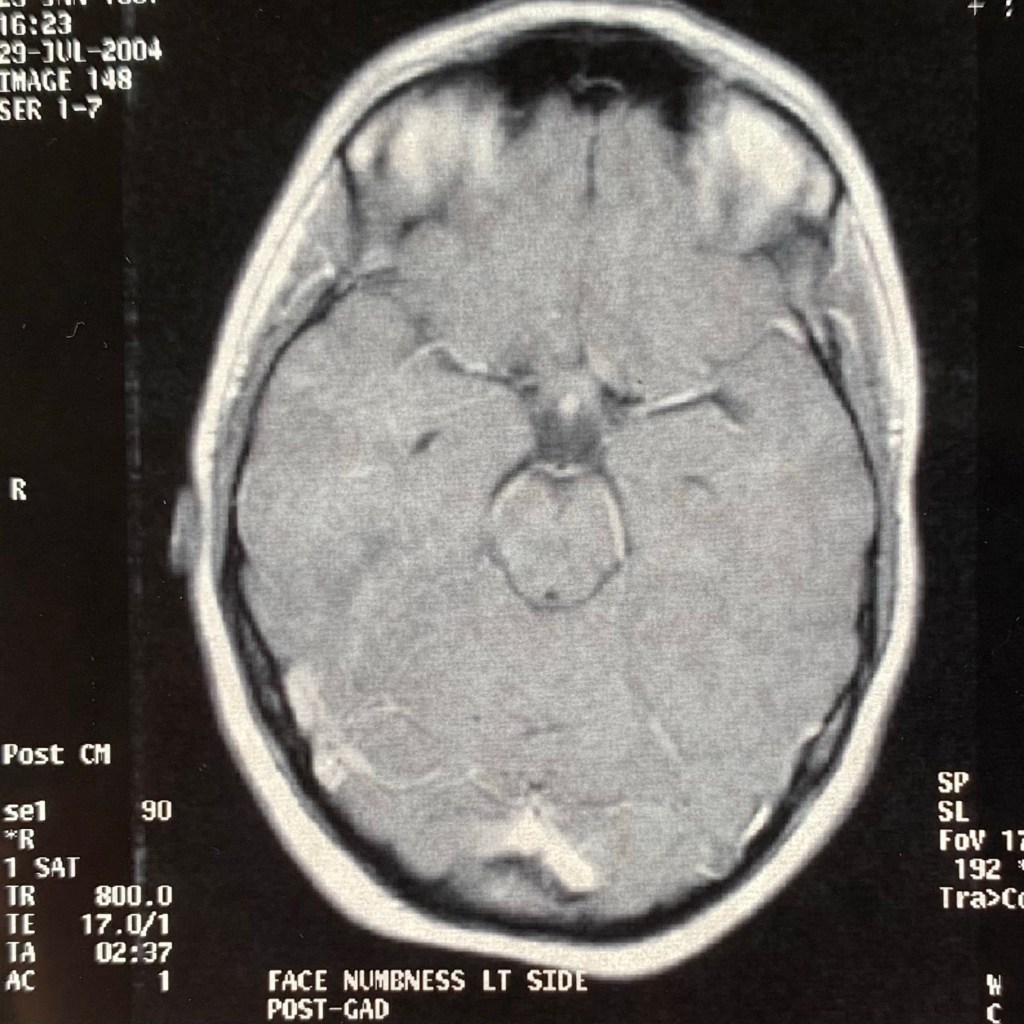

It’s a big year. This year I will have had multiple sclerosis for as long as I didn’t. I was diagnosed in 2004 and 17 years later, here we are. It all started with some numbness on the left side of my face that migrated to my left ear and down my neck. An MRI revealed my “textbook” relapsing-remitting multiple sclerosis with three brain lesions and seven spinal lesions. This diagnosis put the pieces together for some vision problems I had been having and a strange episode of back pain I had as a 15-year-old.